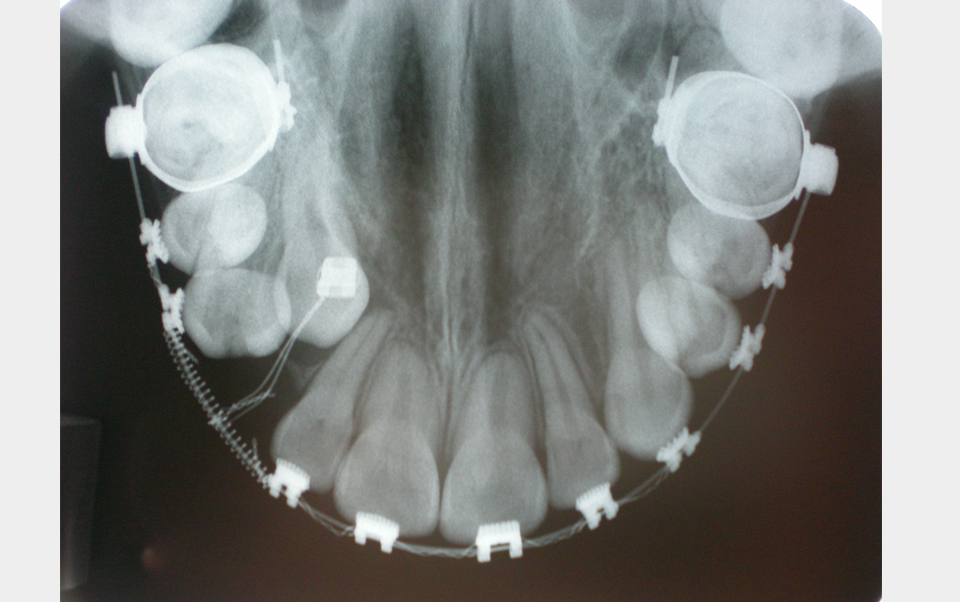

Es una radiografía que complementa muy bien la información obtenida con una Ortopantomografía, especialmente en los casos de lesiones quísticas y tumorales, dientes incluidos, fracturas alveolodentarias, cálculos en el conducto de Warthon, dientes supernumerarios etc.